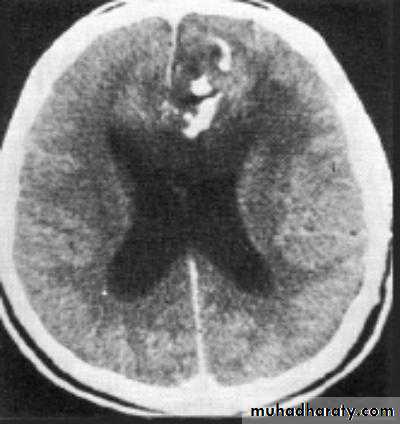

• Computed Tomography scan (CT scan) with/without contrast• Magnetic Resonance Imaging (MRI) with/without contrast